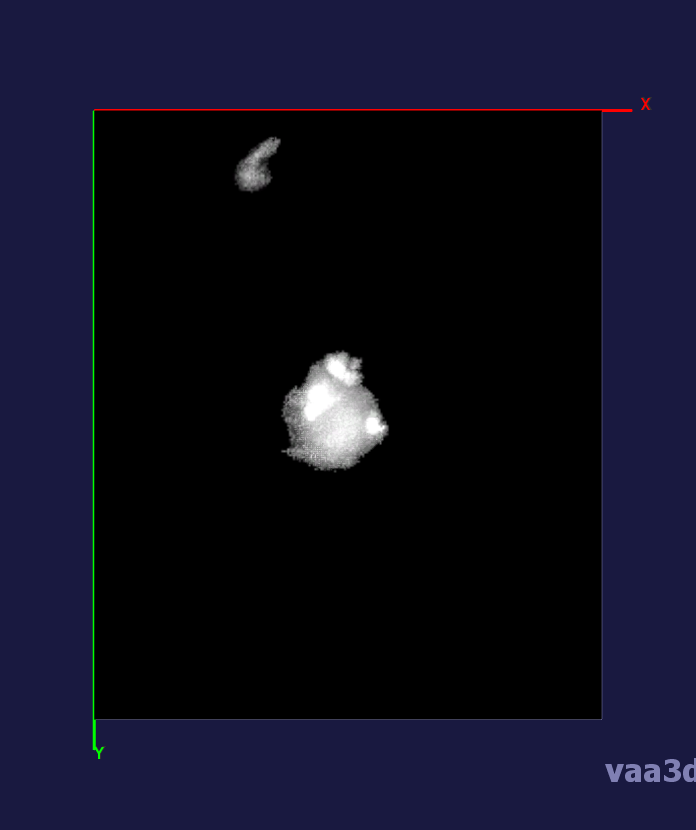

In our experiments, we compare the coupled TuFF-BFF microglia segmentation results with those given by L2S [21] and the Chan-Vese segmentation method [22]. The groundtruth in 3D was attained by manually tracing the object slice by slice from the z-stack. It must be noted that this was done by eye and could have some error. Figure 2 shows the visual comparison of the segmentation results for our dataset. Our result shown on the third column captures both the soma and processes. Figure 3 shows the Dice coefficient comparison of each segmentation method to the ground truth. Since the soma is much larger than the fine processes in the microglia, the processes have less volumetric impact on the similarity score. As explained in Section 1, segmenting the processes is important for quantifying the extension from the soma and its volume of surveillance. We use the Dice coefficient to quantitatively compare the ramification by taking the convex hull of the resulting segmentation. The Dice coefficient is a similarity measure that is computed using with where is the ground truth and is the compared image.

From Figure 4, the average Dice score for coupled TuFF-BFF was 0.77, compared to 0.53 for L2S [21] and .58 for Chan-Vese [22]. It must be noted that L2S required manual user initialization for each 2D image in the stack. While the Chan-Vese method has automatic seed selection, our coupled TuFF/BFF method was the only method that was a true 3D segmentation algorithm. L2S could not consistently capture the entire processes due to the intensity inhomogeneity throughout the object and background noise. The Chan-Vese segmentation could capture the extensions of the processes but did not work well with noise and attained false positives in the reconstruction. Since our method uses the tubular and blob information of the object to separate foreground and background, the segmentation only evolved within the object boundaries.